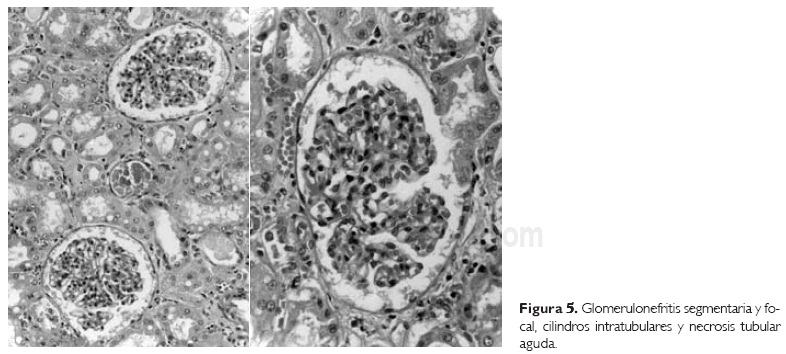

Los riñones mostraron puntilleo hemorragia) en la médula y los cortes histológicos revelaron glomeruloesclerosis segmentaria y focal, así como nefritis túbulo intersticial (Fig. 5); estas alteraciones son frecuentes en los pacientes infectados con VIH. En las glándulas suprarrenales había adrenalitis focal y algunas células mostraban alteraciones compatibles con infección viral; sin embargo, no se observaron inclusiones. La médula ósea mostraba hipoplasia leve de las tres series, y los testículos mostraban atrofia de los túbulos seminíferos y fibrosis intersticial.

7. Glomeruloesclerosis segmentaria y focal.

8. Nefritis túbulo intersticial.

a. Necrosis tubular aguda.